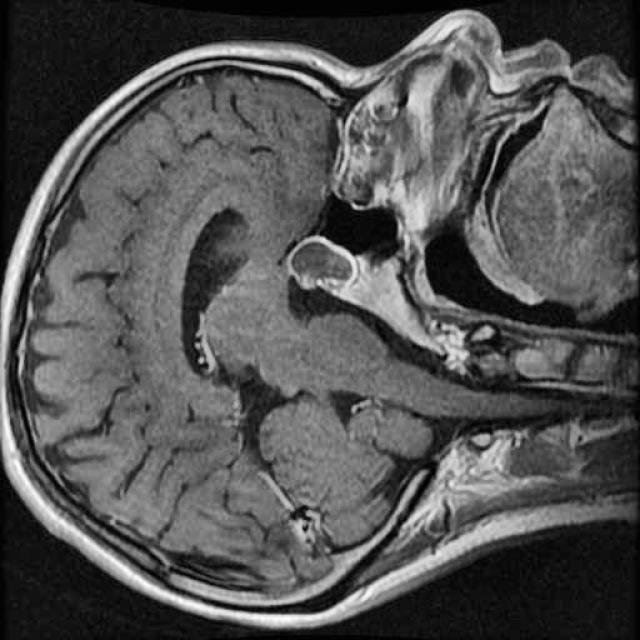

In this demo, we will build our first segmentation model using OneAI. Unlike classification or object detection, segmentation assigns a class label to every individual pixel of an image. This makes it particularly well suited for medical imaging tasks, such as identifying tumor regions in MRI scans.

The goal of this tutorial is to demonstrate how a brain tumor segmentation model can be trained using only 50 MRI images. The focus is not on achieving state-of-the-art medical performance, but on showing how quickly and efficiently a segmentation workflow can be set up and trained with OneAI.

For this tutorial, we use a small dataset consisting of 50 MRI images of the human brain.

These images were selected from a larger Roboflow dataset containing many more samples annotated in an object detection format. You can find the original dataset here.

Even with a relatively small dataset, segmentation combined with targeted augmentations can extract useful spatial information and allow us to train a functional model.